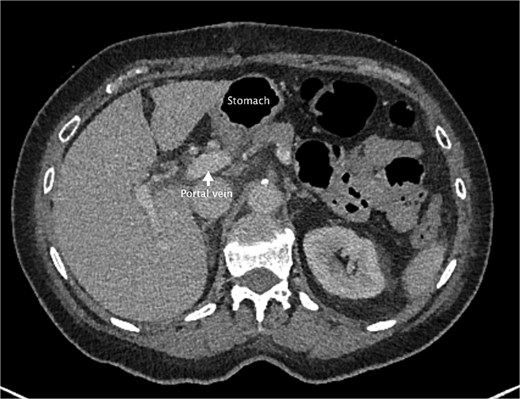

She had a computed tomography (CT) abdomen and pelvis in the emergency department, which was initially reported as mesenteric panniculitis. She had an initial lactate of 3.3 mmol/l (reference range < 2.0), other blood tests, including white cell count and hemoglobin level, were normal. C-reactive protein was also normal. She was referred to the surgical team in the morning to determine a follow-up plan as her pain had improved and she was planned to be discharged home. On review by the surgical team, she was clinically well, her abdomen was soft and not tender on examination. However, on review of the CT images, there appeared to be a dilated segment of colon in the right upper quadrant, and on further analysis, it appeared to be a Foramen of Winslow hernia containing colon. There was also an area that appeared to demonstrate a potential filling defect in the portal vein along with periportal oedema. This raised the concern of a potential thrombus versus vascular congestion (Figs 1 and 2).

An axial slice from the pre-operative CT abdomen pelvis in portal venous phase. There is an arrow pointing to narrowed appearance of portal vein. Also labeled are the herniated colon anteriorly and the stomach to the left of the herniated colon.